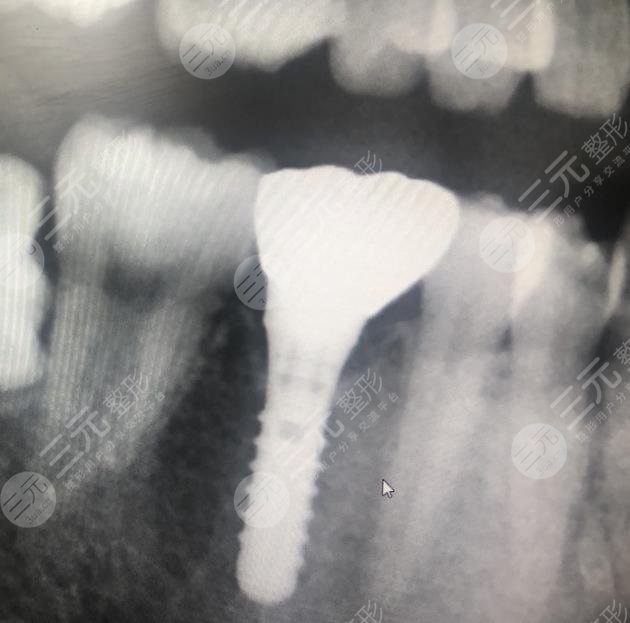

我的牙齿有一颗牙齿坏了很久了,所以我一直想要修复,但是我又不想拔掉,所以就很纠结,不知道怎么样的方式才能够改良,经过朋友的一番介绍说,我还是选择到口腔医院里面检查一番,然后再决定具体的缓解方法。在和口腔医院的医生沟通之后,他说像我这种方情况必须要把原有的坏牙拔掉之后换新的牙齿,不会有口腔造成疾病的情况。

在听了医生的介绍之后,我决定选择使用这种方法,没想到这种方法确实GET了不错的目的,现在我种植牙齿之后已经有快两年的时间了,没有出现任何的副作用,平时也没有出现牙齿疼痛的现象。